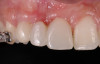

A healthy 20-year-old woman presented to the author’s office requesting treatment for a large defect in the area of missing tooth No. 7. She exhibited a high smile line that revealed a clearly visible deformity, associated with pain and sensitivity on teeth Nos. 6 and 8 and in the area of tooth No. 7 (Figure 1). Although the patient wore a modified Essix retainer, the defect was still visible because of the magnitude of tissue loss and the revealing nature of her smile.

Fig 1. The patient presented with a large deformity stemming from a congenitally missing maxillary right lateral incisor.

Figure 1